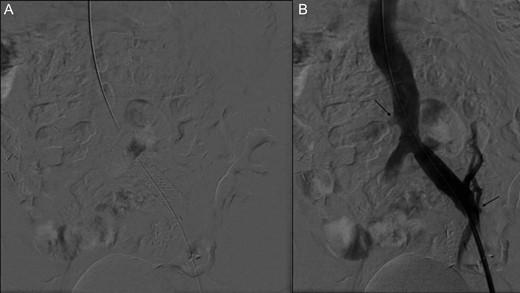

(A) Stent placement (B) Angiography post-thrombectomy and stent showing intact runoff to pancreatic and renal allografts (arrows).

Two months after her transplant she developed abdominal pain and a CT scan was performed. Imaging demonstrated an extensive thrombus in the left common and external iliac veins, with compression of the left common iliac vein superior to the thrombus (Fig. 2). An interventional cardiology team performed angiography which showed a 100% occlusive lesion in the left CIV, with thrombotic defect in the left EIV, and patent pancreatic SMV and left renal vein. Balloon angioplasty and combined Angiojet and manual thrombectomy of the left common and external iliac veins was performed. A 16 mm x 40 mm Wallstent self-expanding metal stent was deployed in the left CIV, with a proximal landing site in the IVC, just distal to the pancreatic vein graft. Post-procedure angiography demonstrated a 30% residual stenosis, with patent flow through the LCIV and LEIV, and both the pancreatic and renal grafts. She was started on therapeutic anticoagulation after the procedure. Surveillance imaging 6-months post-procedure demonstrated no residual clot burden and appropriate stent positioning. Labs at 1 year follow up show persevered allograft function, with creatinine 0.91, amylase 88 and lipase 140, and no insulin requirements.